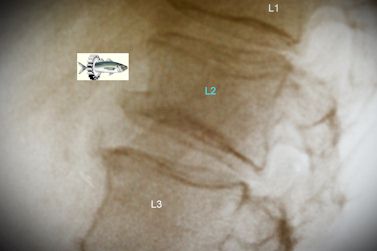

Liste de vertèbres lombales (ou lombaires)

Les vertèbres lombales (ou lombaires) sont cinq vertèbres de la base de la colonne vertébrale. Elles se situent sous les vertèbres thoraciques et au-dessus du sacrum. La cinquième vertèbre lombale (L5, la plus caudale) s'articule avec celui-ci pour constituer la charnière lombo-sacrée, jonction entre la partie mobile et la partie fixe de la colonne. Les vertèbres lombales sont les vertèbres les plus robustes, car elles doivent supporter plus de poids que toutes les autres.

Ex: "Suède. Eté 2010. Sous les assauts répétés des vagues et avec un grand craquement, ma vertèbre L2 céda. René et les filles se mirent à hurler." Mémoires d'un explorateur-programmeur